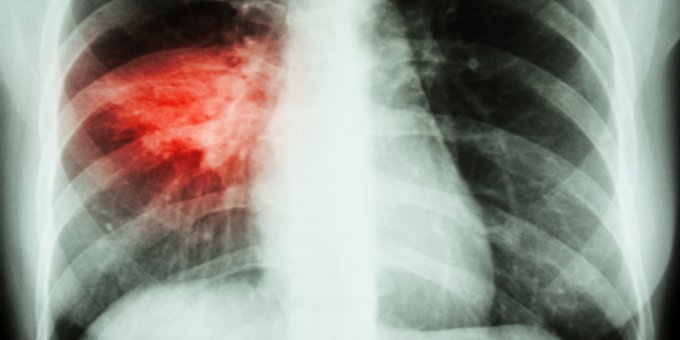

Lo + visto de la semana en MedlinePlus en español: Neumonía ow.ly/eY8l50A26sc